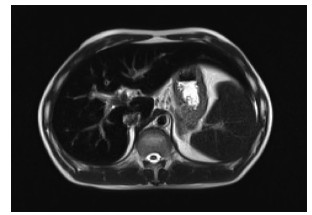

Two cases of ulcerative colitis with liver injury

Hao WU, Man LIU, Na LI, Dan CHEN, Lei ZHU

2021, 37(5): 1171-1173. DOI: 10.3969/j.issn.1001-5256.2021.05.038

Abstract(1026) HTML (364) PDF (3754KB)(67)

Abstract: